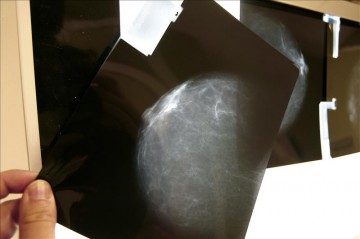

El proceso da comienzo cuando una mujer acude al hospital por recomendación de su médico de cabecera para hacerse una mamografía o una biopsia.

En el último caso, la muestra es enviada al laboratorio de Anatomía Patológica, que realizará el análisis de tejidos para determinar si hay o no cáncer de mama.